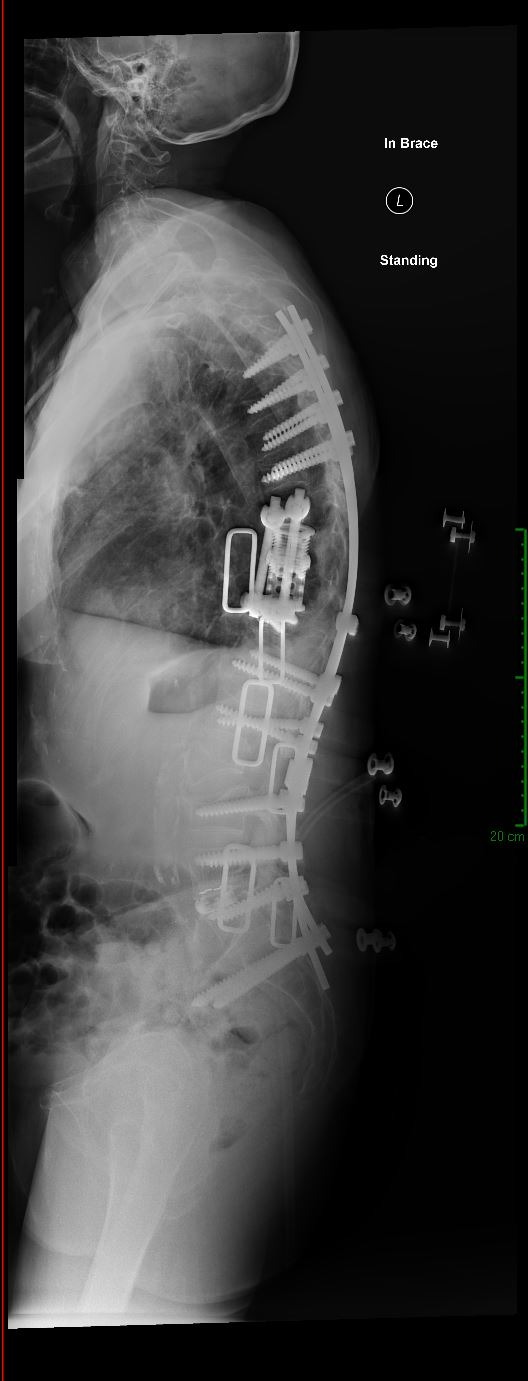

Imaging Gallery

Before & After

Spine Surgery

All imaging is fully de-identified. Patient identifiers removed in compliance with HIPAA.